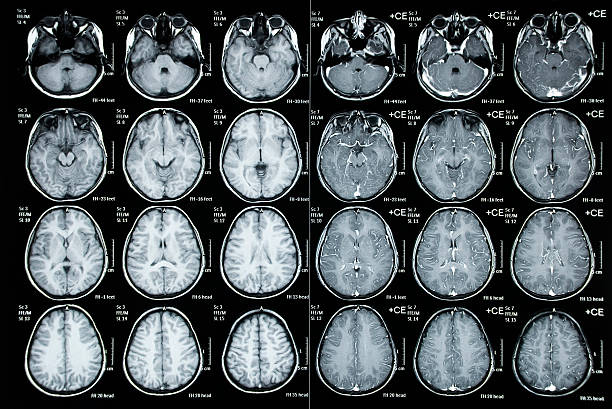

뇌동맥류는 뇌의 혈관이 벽의 약한 부분이나 손상으로 인해 팽창하거나 부풀어 오른 상태를 말합니다. 뇌동맥류는 일반적으로 증상이 없으며, 우연히 발견되기도 합니다. 그러나 뇌동맥류가 크거나 위치가 민감한 경우, 심각한 증상을 초래할 수 있어 이번 시간에는 뇌동맥류로 나타나는 증상에 대해 자세히 알아보도록 하겠습니다.